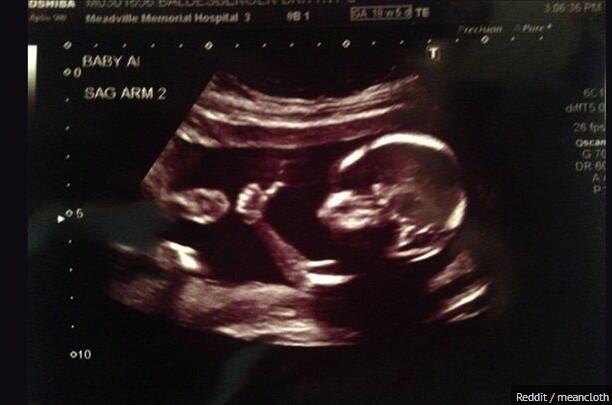

网友晒胎儿竖大拇指b超照片引关注

准爸爸欧弟晒娇妻怀孕b超照网友调侃小欧弟要1米九九组图